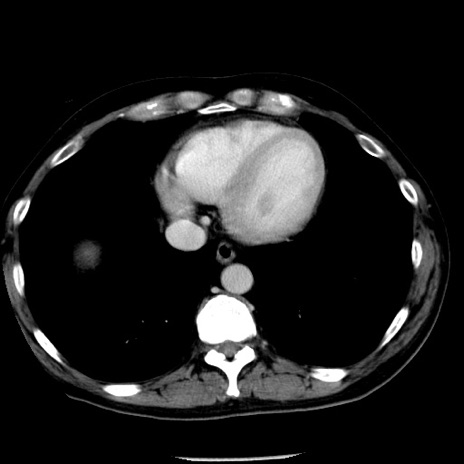

症例29(横断像)

【症例】40歳代男性

【現病歴】2日前から胃痛あり。徐々に周期的な激痛に変化した。本日になっても激痛があるため受診。

【身体所見】意識清明、BT 38-39℃台あり、腹部:膨満、やや硬、右下腹部に圧痛あり。

【データ】WBC 8500、CRP 23.26